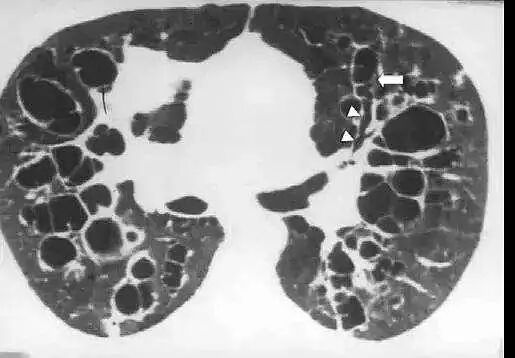

支气管扩张是由于支气管及其周围肺组织慢性化脓性炎症和纤维化,使支气管壁的肌肉和弹性组织破坏,导致支气管变形及持久扩张。典型的症状有慢性咳嗽、咳大量脓痰和反复咯血。